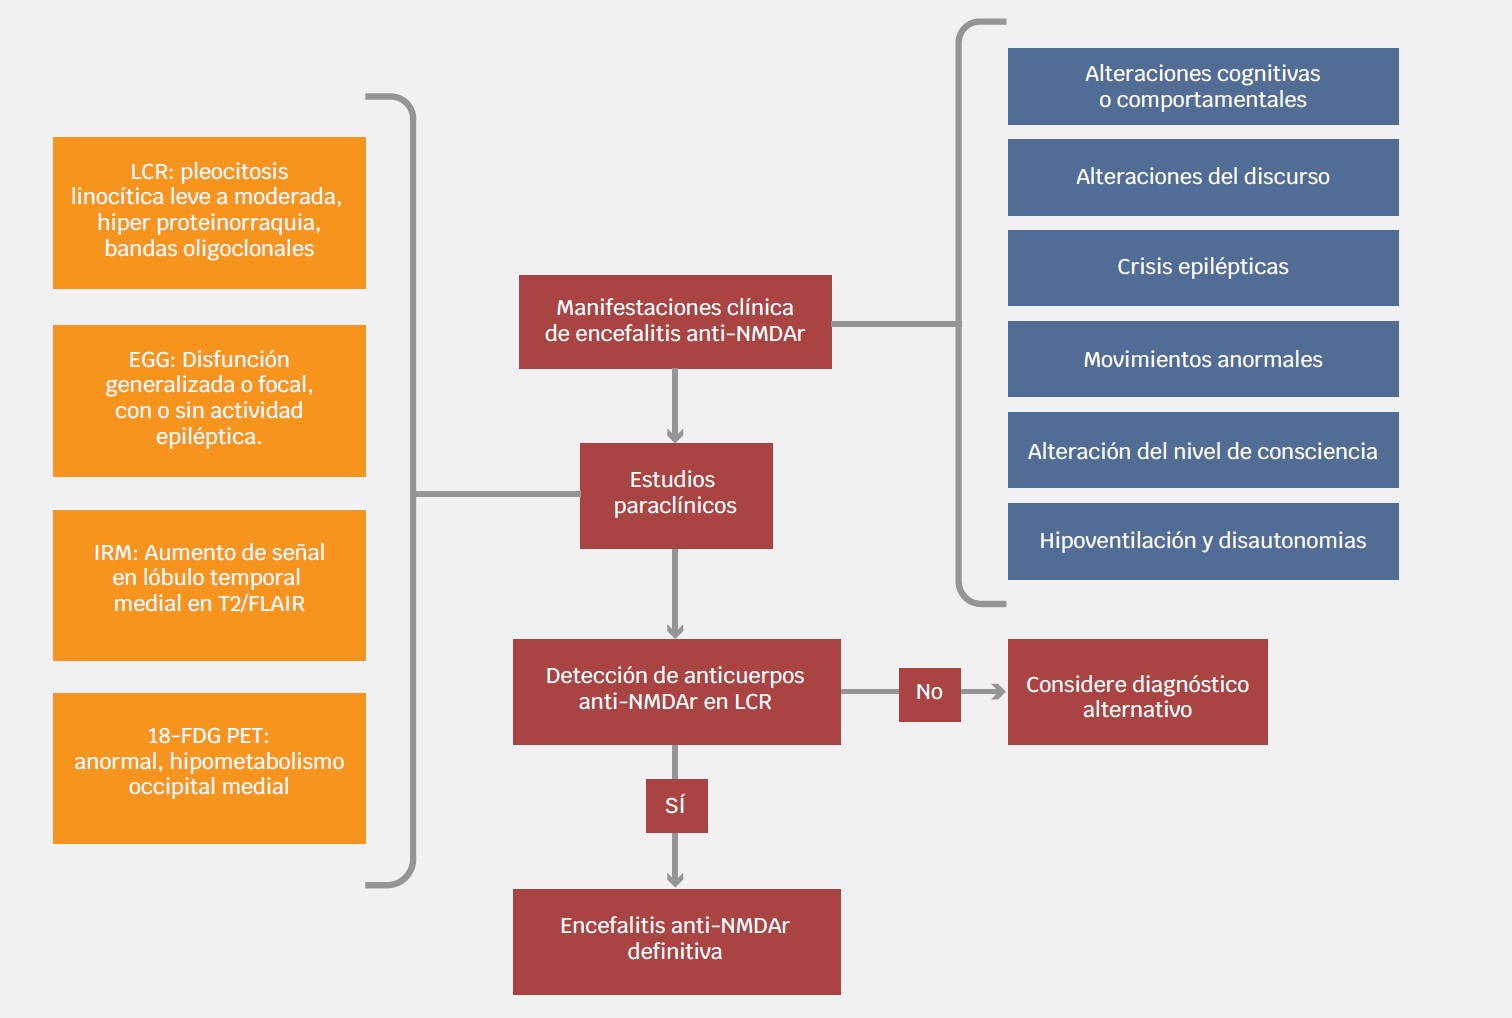

En año 2016, Graus et al. desarrollaron un procedimiento clínico para el diagnóstico de las encefalitis autoinmunes, orientado a seleccionar a los pacientes de tal forma que reciban tratamiento oportunamente. Estos criterios incluyen diferentes niveles de certeza (posible, probable y definitiva) para diferentes entidades inmunomediadas, incluyendo la encefalitis anti-NMDAr. Este abordaje considera una encefalitis autoinmune y antiNMDAr probable cuando los pacientes cumplen los criterios clínicos y paraclínicos expuestos en el Cuadro 2. El diagnóstico de encefalitis anti-NMDAr es definitivo en presencia de uno o más de los seis grupos mayores de síntomas y la demostración de anticuerpos IgG anti-GluN1 en LCR, considerando la exclusión razonable de otros trastornos.3

En el contexto de un cuadro clínico compatible, algunos estudios paraclínicos comúnmente disponibles pueden apoyar el diagnóstico de encefalitis anti-NMDAr. La imagen por resonancia magnética (IRM) cerebral puede demostrar hiperintensidades en la secuencia FLAIR en el lóbulo temporal medial, ínsula, tallo cerebral, ganglios basales o corteza (Figura 2). Ahora bien, hasta 50 % de los pacientes puede tener IRM normal.2

El electroencefalograma (EEG) es anormal en la mayoría de los pacientes (en 85 a 90 %); no obstante, sus hallazgos suelen ser inespecíficos (actividad lenta y desorganizada). En algunos casos, los registros pueden mostrar actividad epiléptica focal o generalizada.2 Treinta por ciento de los pacientes con encefalitis anti-NMDAr presenta un patrón conocido como delta brush extremo (extreme delta brush), asociado a cuadros clínicos más graves y prolongados55,56 (Figura 3).

El análisis del LCR es anormal en 80% de los pacientes al inicio de la enfermedad y cerca de 90% en etapas posteriores.2,57 Este porcentaje podría ser menor: una revisión sistemática de casos reportados estimó que solo 58% de los pacientes presentaba LCR anormal.1 En las fases iniciales de la enfermedad, los estudios de rutina del LCR pueden ser normales, salvo por la presencia de anticuerpos anti-NMDAr. Espinola Nadurille et al., reportan que la presencia de LCR no inflamatorio representa retraso en el diagnóstico correcto y en el inicio de tratamiento inmunomodulador.58

La tomografía por emisión de positrones con 18-fluorodesoxiglucosa (18-FDG PET) debe ser considerada para el diagnóstico de encefalitis límbica cuando la IRM resulta ser normal.3 En la encefalitis anti-NMDAr puede mostrar metabolismo cerebral con gradiente frontooccipital disminuido en regiones mediales de los lóbulos occipitales.59 La utilización de esta herramienta ha sido defendida por algunos autores puesto que puede ser útil para el diagnóstico y en la búsqueda de tumores asociados. Si bien la detección del anticuerpo anti-NMDAr en el LCR es el biomarcador de elección, el hipometabolismo occipital medial puede ayudar en el abordaje y seguimiento de los pacientes59 (Figura 4). La Figura 5 resume cómo realizar el procedimiento diagnóstico de los pacientes con sospecha de encefalitis anti-NMDAr.